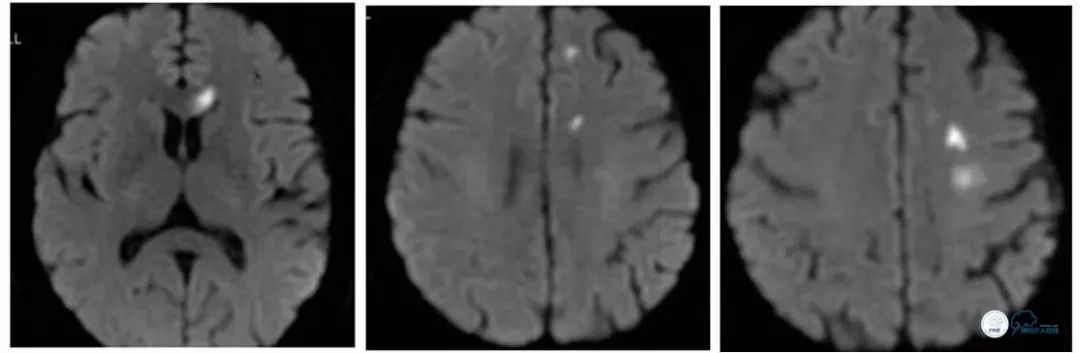

就诊当地医院,行头颅核磁(2018-4-18):左侧胼胝体膝部、左额顶叶新鲜脑梗死(图1)。

图1